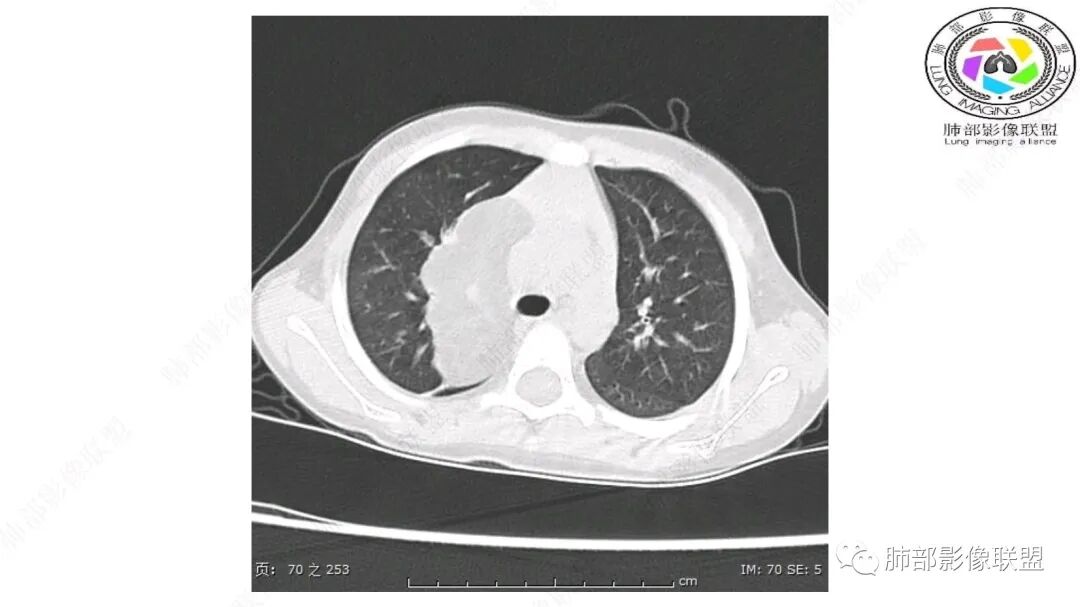

患儿3岁 咳嗽检查发现纵隔占位。右肺上叶受压表现,占位以脂肪组织密度为主,似见分隔,首先考虑为脂肪母细胞瘤,鉴别脂肪瘤,畸胎瘤。

病灶属于交界区,主体位于肺内,占位效应明显,前方突入胸壁,胸腺受压变形,胸膜显示欠清楚;病灶包绕上叶肺动脉;似乎有体动脉供血。符合肺内的点:包绕上叶肺动脉分支;符合纵隔的点:前方似乎突入胸壁,与胸腺关系比较密切,但是与上腔静脉的关系提示病灶不支持纵隔来源,前纵隔的常规会将上腔静脉受压后移、外移,这是不符合的。

手术记录:见右肺上叶肿物,肿物与右肺上叶关系密切。与纵隔无粘连,逐步分离肿物,见肿物大小约6cm*5cm,边界清楚,于右肺上叶粘连,边界清楚,肿物包绕右肺上叶血管及支气管。超声刀逐步游离肿物,完整切除肿物,右肺上叶肺组织无破溃,表面无出血。

CT扫描对脂肪类肿瘤常有独到价值。肿块孤立、边界清楚,未见周围浸润,较均匀脂肪样低密度,高度提示为良性!

发生于成人为脂肪瘤表现,婴幼儿自然会想到脂肪母细胞瘤。两者生物学行为并无本质区别。